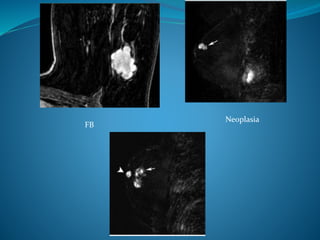

Neoplasia FB.

Neoplasia

FB

2) Masas: lesiónque ocupa un espacio dentro de la mama. Se describe: • Forma:  Redonda  Oval  Lobulada  Irregular quiste Malignidad